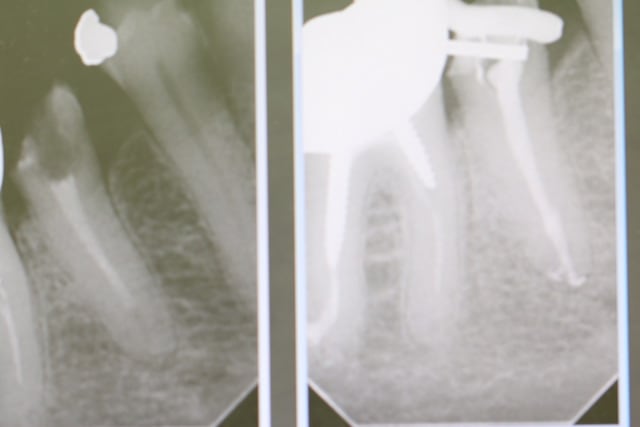

L'équipe gagnante de l'endo taille empreinte version turbo (30 mn) dans la séance.......

(+ quick sleeper, + endomaster)